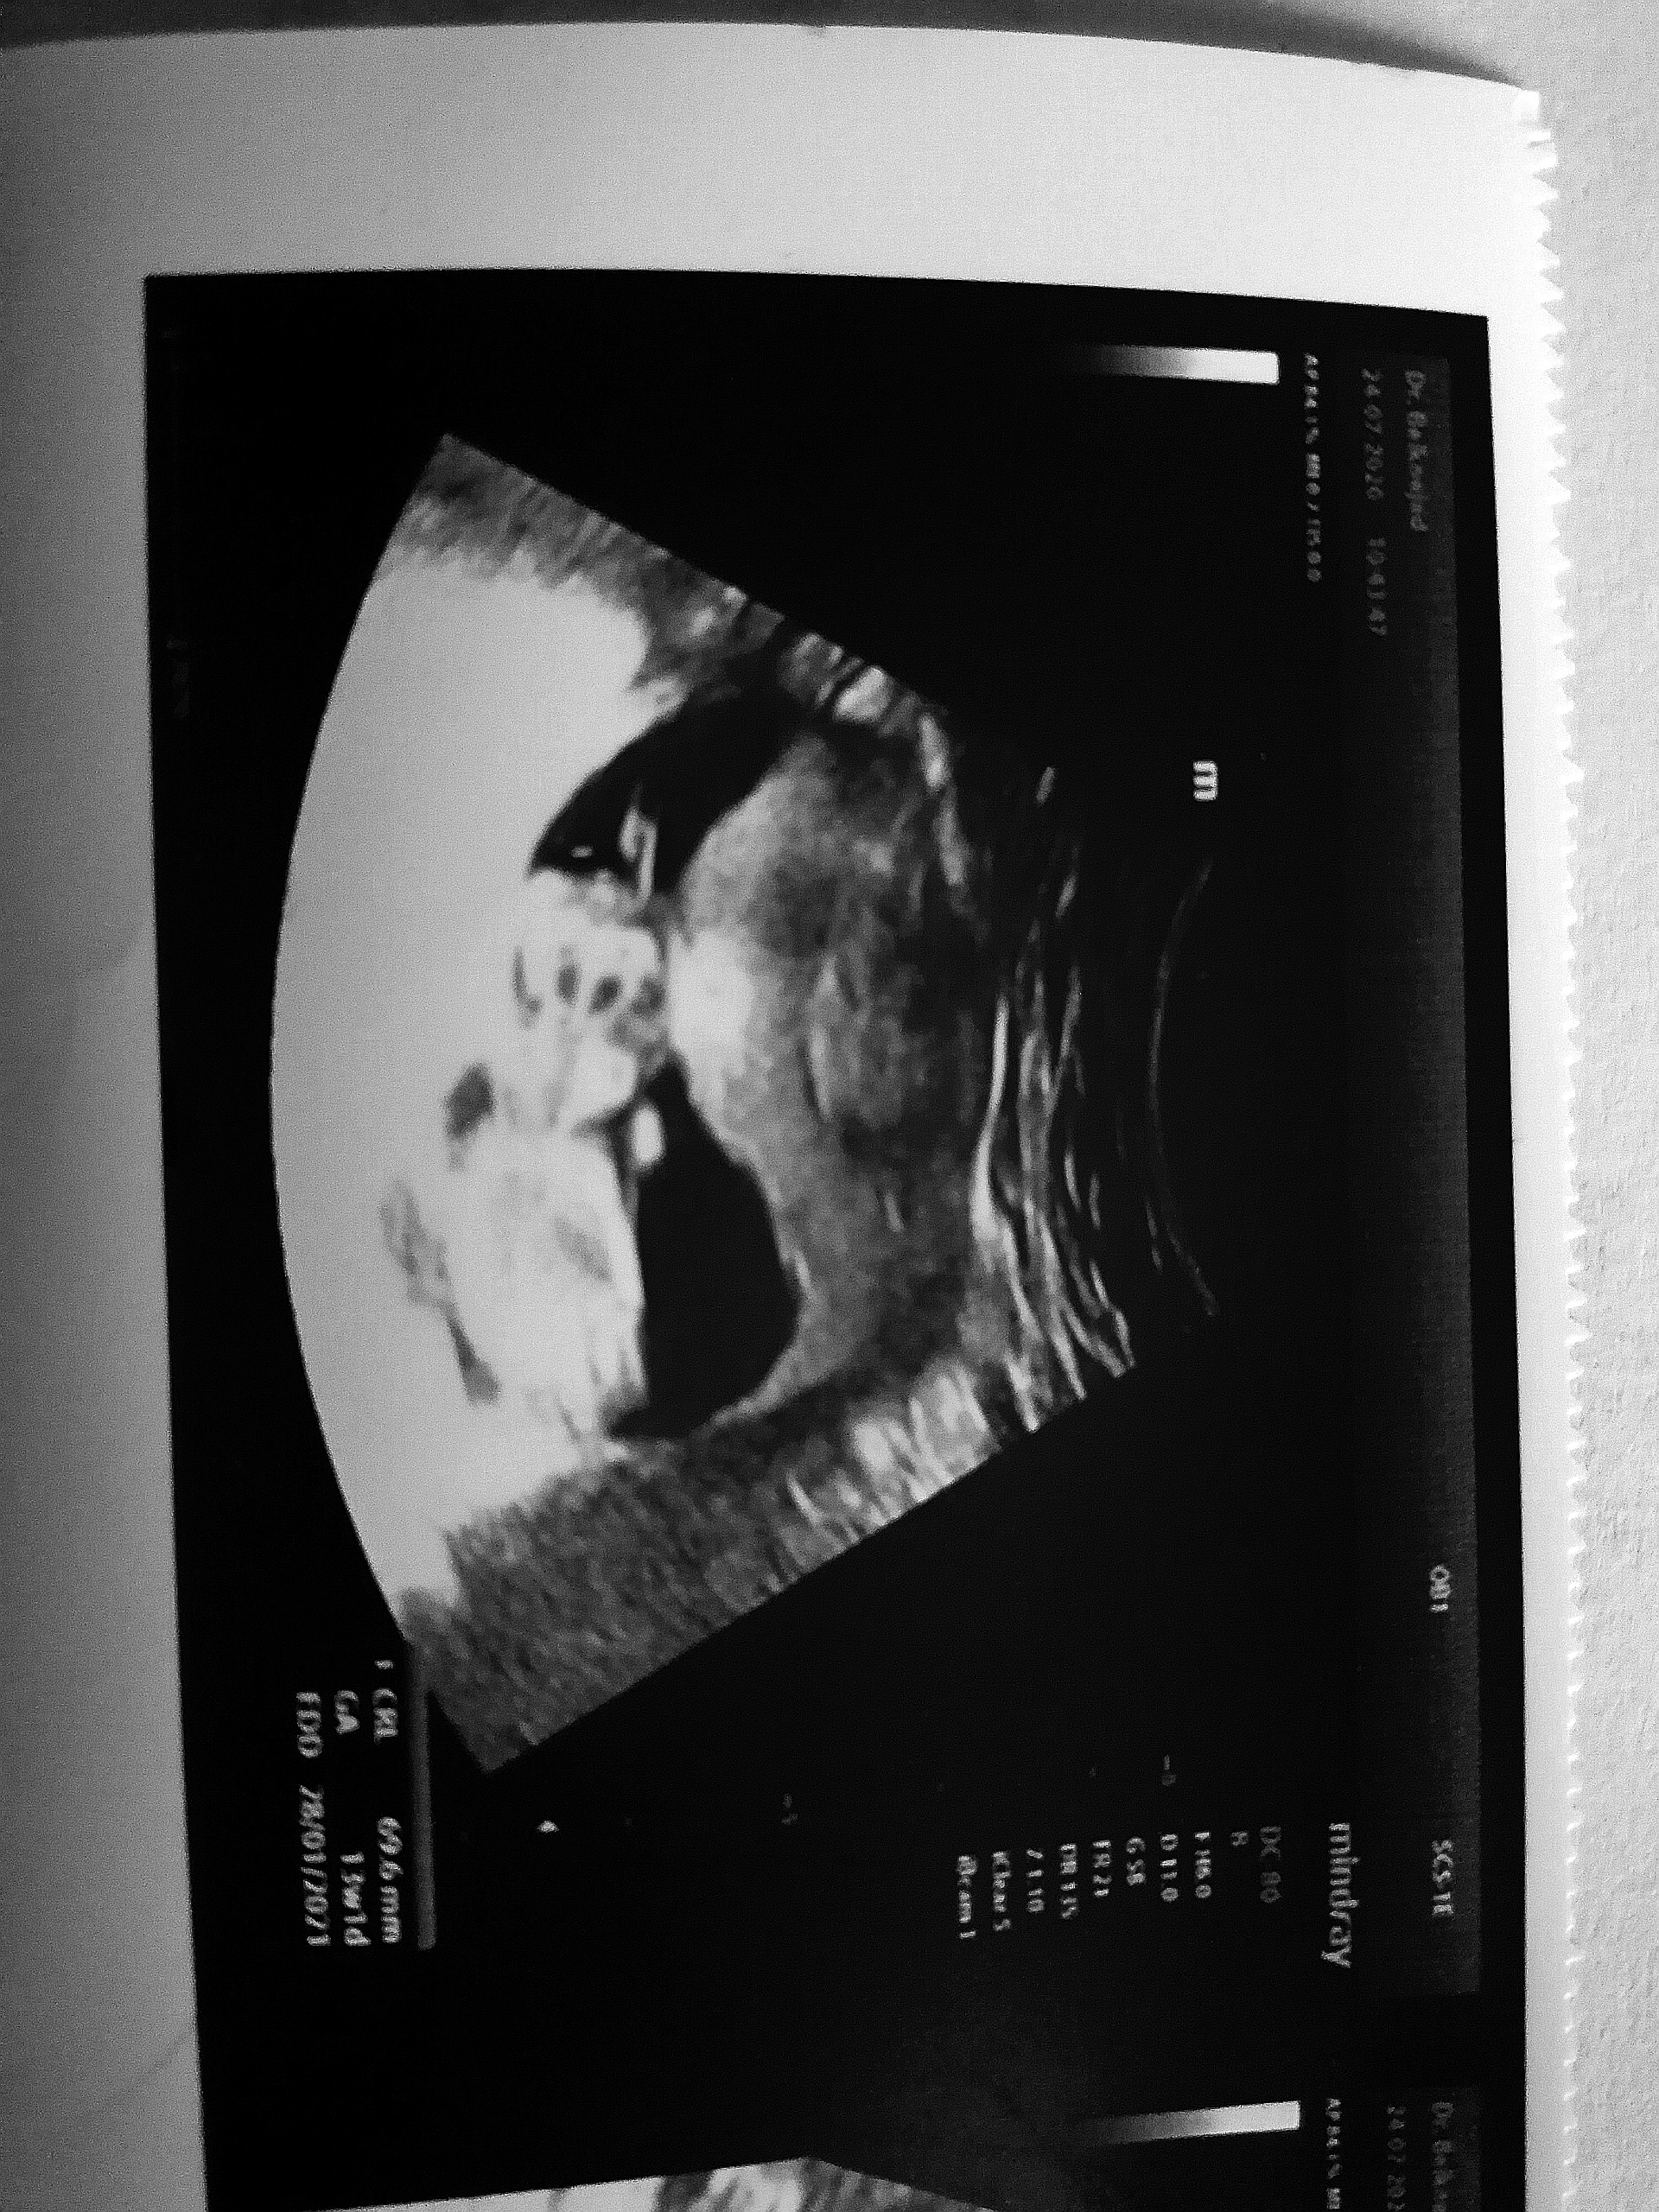

andiyya مدیر عضویت: 1396/07/22 تعداد پست: 311 عنوان جنسیت نی نی 😍 | مشاهده متن کامل بحث + 236 بازدید | 30 پست بنظرتون چیهان تی گفت احتمال زیاددختره 1400/07/27 | 13:20 1 نفر لایک کرده اند ... گزارش تاپیک نامناسب

andiyya مدیر استارتر عضویت: 1396/07/22 تعداد پست: 311 منم دوهفته دیگه میرم.مبارک باشه عزیزم.شما ۱۲ هفته رفتین؟ فداتشم ۱۳هفته رفتم

andiyya مدیر استارتر عضویت: 1396/07/22 تعداد پست: 311 برا من ضربان قلب درست بود تقویم چینی غلط بنظرمن همه ایناجنبه سرگرمی دارهسونوگرافی فقط تعیین میکنه جنسیت رو